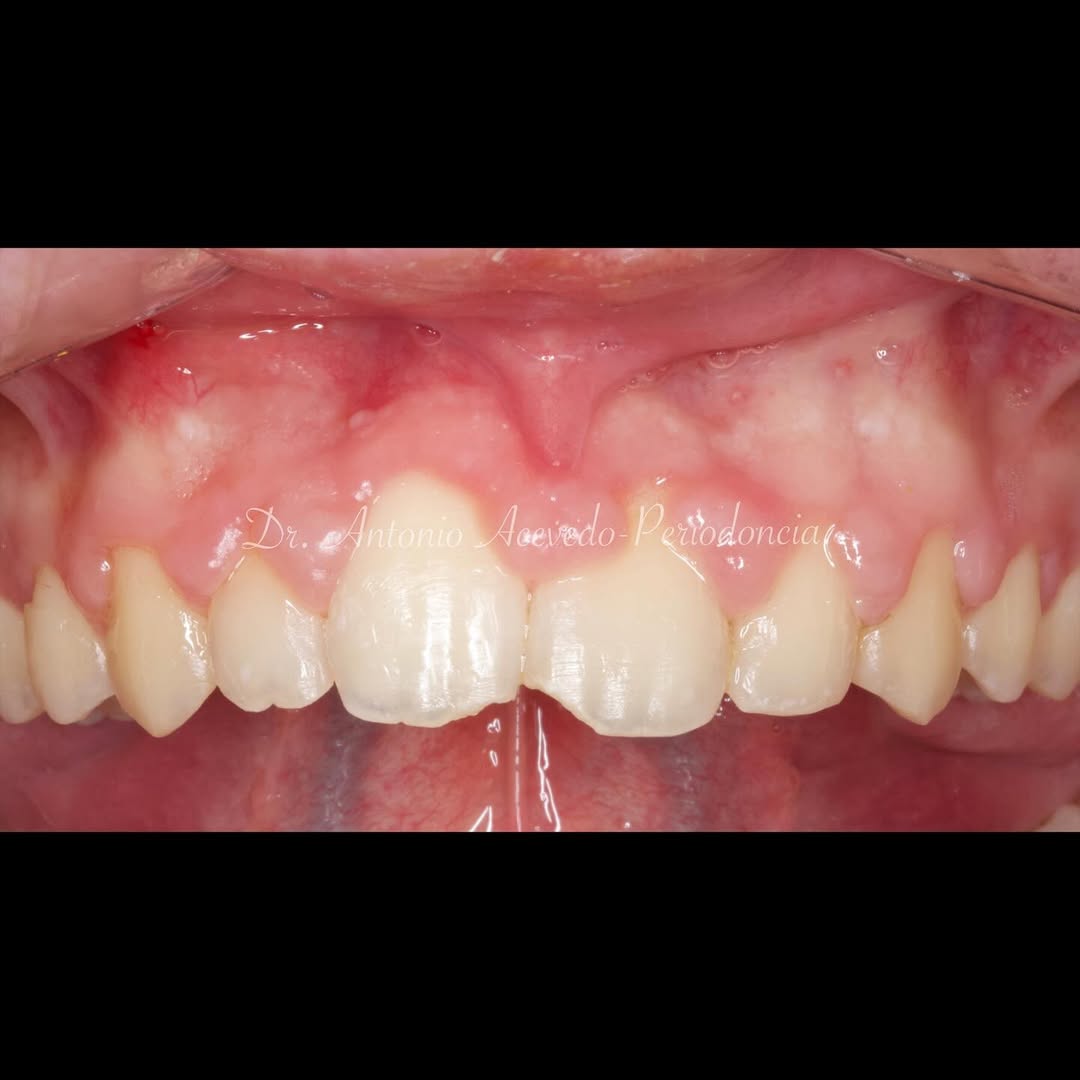

Ya se han realizado la extracción de los dientes 12, 11, 21, 22 para garantizar el cierre de tejidos blandos. El día de la cirugía, el alumno verá todo el procedimiento en una pantalla en directo en la sala de cirugía, ya que todo será realizado con un microscopio operatorio.

Se extraerán los